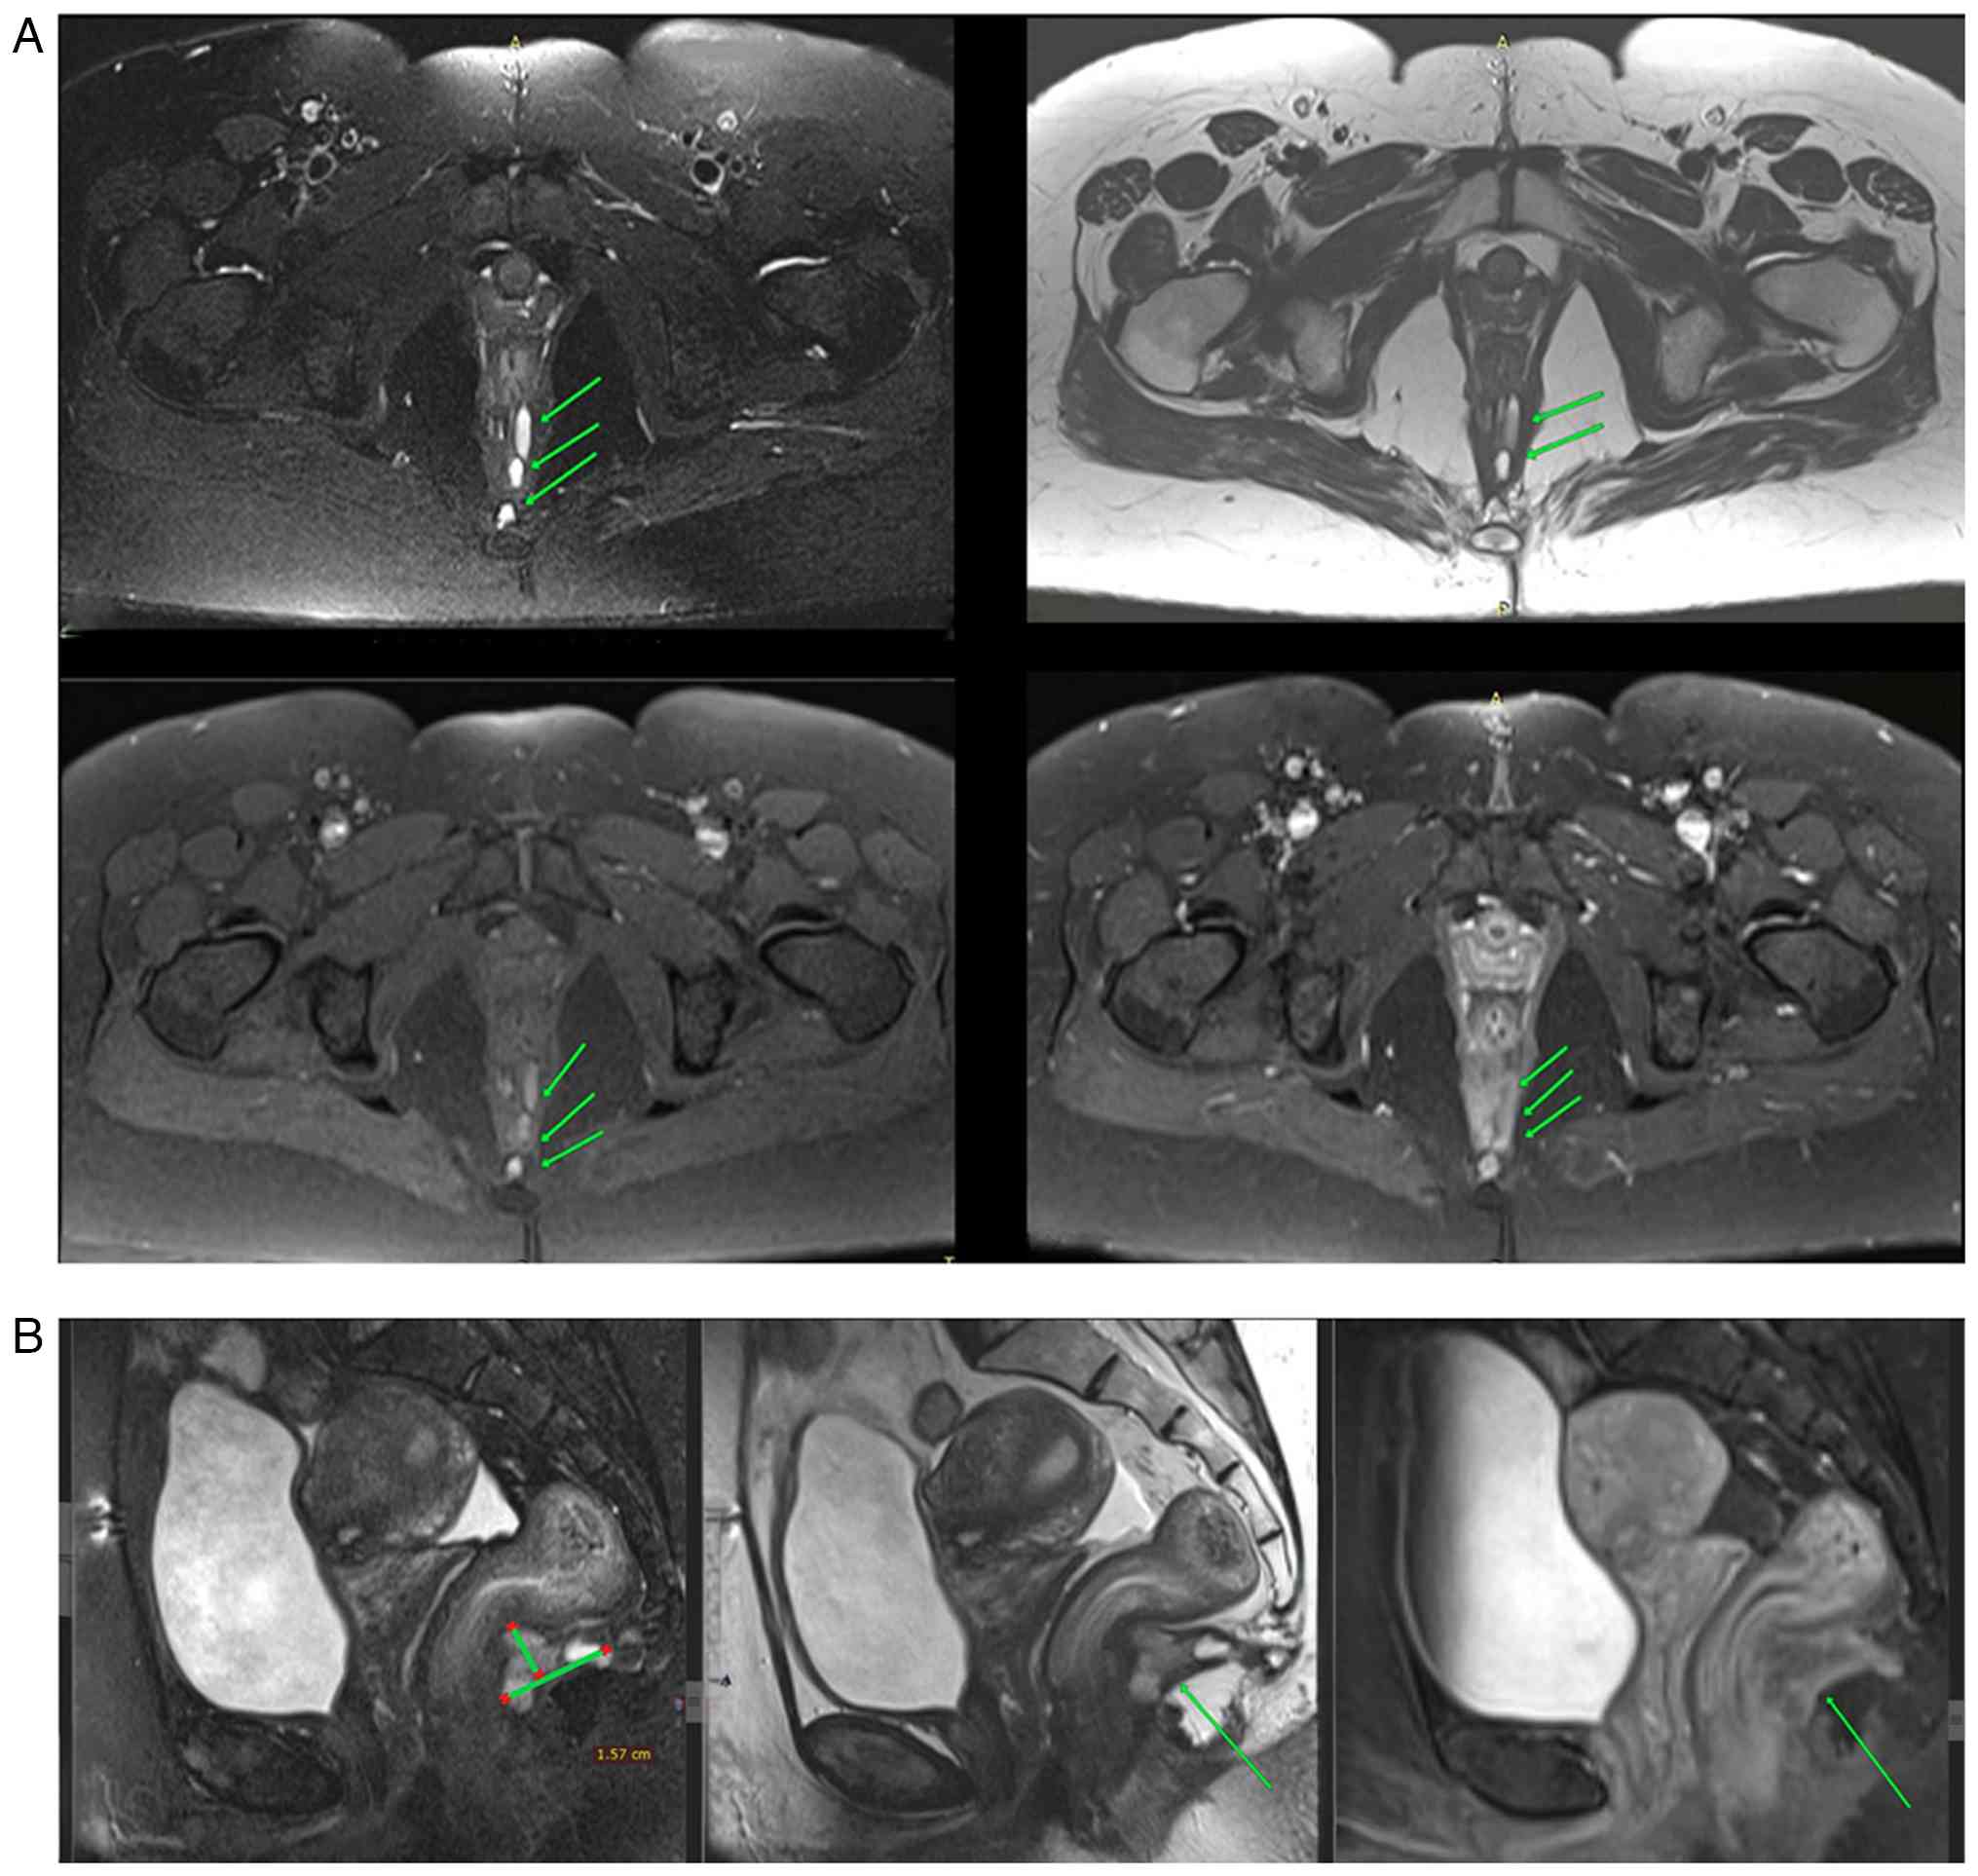

Blood investigations revealed a normal complete blood count. Stool calprotectin was measured at 20.2 µg/g (normal range, <50 µg/g), excluding active inflammatory bowel disease. Trans-perineal ultrasonography identified a single external opening at the 6 o'clock position at the anal verge, from which a tract extended into the intersphincteric plane. A multiloculated, thin-walled cystic lesion, measuring 25x16x10 mm, was identified posterior to the anal canal. The absence of direct communication with the rectal or anal canal lumen suggested an extra-luminal origin. A magnetic resonance imaging (MRI) was conducted and confirmed the presence of a multiloculated cystic lesion, measuring 30x16x15 mm, situated in the presacral region, anterior to the distal rectum, and extending towards the anorectal junction. The cyst was thin-walled and lacked solid components, with no connection to the rectal lumen (Fig. 1). Furthermore, the MRI revealed an associated complex perianal fistula, classified as grade II according to the St. James's Hospital Classification. An ileo-colonoscopy revealed patchy areas of colitis, and multiple biopsies were obtained. A histopathological analysis was performed on 5-µm-thick paraffin-embedded tissue sections. The sections were fixed with 10% neutral buffered formalin at room temperature for 24 h and then stained with hematoxylin and eosin (H&E; Bio Optica Co.) for 1-2 min at room temperature. The sections were then examined under a light microscope (Leica Microsystems GmbH). The histopathological examination revealed no notable abnormalities, effectively ruling out inflammatory or neoplastic conditions (data not shown).

(A) Axial section images [images on

the upper panel (left panel, T2-weighted fat-saturated; right

panel, T2-weighted); images on the lower panel (left panel, T1

fat-saturated pre-contrast; right panel, T1 fat-saturated

post-contrast)] illustrating an elongated multiloculated

thin-walled cystic lesion in the presacral space (green arrows),

extending from the posterior aspect of the rectum toward the

sacrococcygeal region while rectum and vertebrae are normal with no

surrounding soft tissue edema. (B) Sagittal plane images (left

panel, T2-weighted fat-saturated; middle panel, T2-weighted; right

panel, T1 fat-saturated post-contrast) illustrating a presacral

space lesion (green arrows), which is above the pelvic diaphragm

and extending toward the anorectal junction.

Figure 1

(A) Axial section images [images on the upper panel (left panel, T2-weighted fat-saturated; right panel, T2-weighted); images on the lower panel (left panel, T1 fat-saturated pre-contrast; right panel, T1 fat-saturated post-contrast)] illustrating an elongated multiloculated thin-walled cystic lesion in the presacral space (green arrows), extending from the posterior aspect of the rectum toward the sacrococcygeal region while rectum and vertebrae are normal with no surrounding soft tissue edema. (B) Sagittal plane images (left panel, T2-weighted fat-saturated; middle panel, T2-weighted; right panel, T1 fat-saturated post-contrast) illustrating a presacral space lesion (green arrows), which is above the pelvic diaphragm and extending toward the anorectal junction.